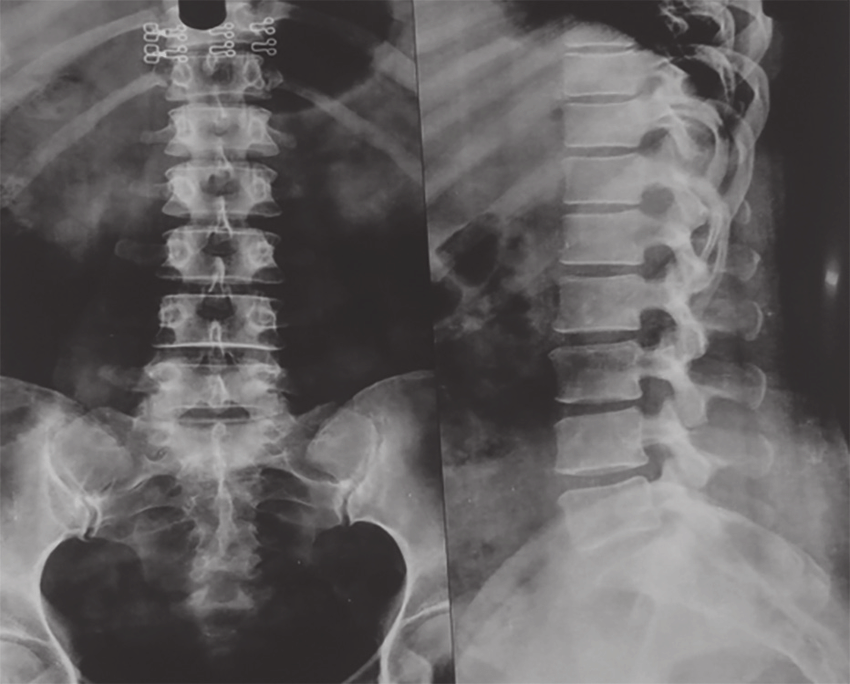

Damn good lifting advice. That’s a serious procedure, stay careful Man. At least you got to see your own insides on those X-rays though. That’s pretty cool. Keep that skeleton in check